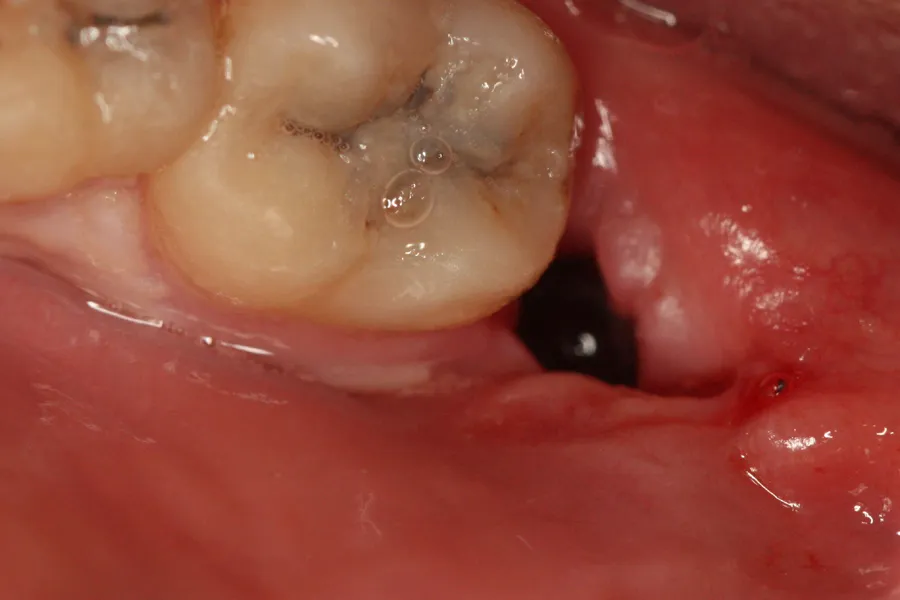

Skrzep krwi: Twój naturalny opatrunek, którego kawa nie lubi

Bezpośrednio po wyrwaniu zęba w miejscu ekstrakcji tworzy się skrzep krwi. Jest to naturalny i niezwykle ważny element procesu gojenia. Skrzep stanowi barierę ochronną dla odsłoniętej tkanki kostnej i jest fundamentem, na którym rozpoczyna się proces odbudowy. Gorąca kawa, swoją wysoką temperaturą, może negatywnie wpłynąć na stabilność tego delikatnego skrzepu. Może doprowadzić do jego rozszerzenia, a w skrajnych przypadkach nawet do jego oderwania lub rozpuszczenia, co otwiera drogę do bolesnych powikłań.

Suchy zębodół: bolesne powikłanie, którego unikniesz

Suchy zębodół to jedno z najczęściej występujących i najbardziej nieprzyjemnych powikłań po ekstrakcji zęba. Jego wystąpienie jest zazwyczaj bezpośrednio związane z utratą lub zaburzeniem formowania się skrzepu krwi w miejscu po usuniętym zębie. Na szczęście, poprzez odpowiednie postępowanie i unikanie pewnych nawyków, można znacząco zmniejszyć ryzyko jego pojawienia się.

Co to jest suchy zębodół i dlaczego jest tak nieprzyjemny?

Suchy zębodół, medycznie określany jako alveolitis sicca, to stan, w którym w miejscu po wyrwanym zębie brakuje skrzepu krwi lub został on przedwcześnie usunięty. Bez tej naturalnej bariery ochronnej, odsłonięta zostaje kość zębodołu. Powoduje to silny, często pulsujący ból, który może promieniować do ucha, skroni lub szyi. Jest to stan bardzo bolesny i wymaga interwencji stomatologicznej, która często polega na oczyszczeniu zębodołu i podaniu leków łagodzących ból oraz przyspieszających gojenie.